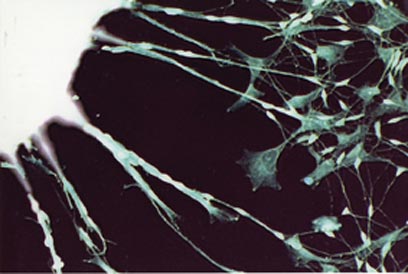

תאי גזע שעברו תכנות מחדש באמצעות רנ"א, מגדלים שלוחות ארוכות האופייניות לתאי עצב (מכון ויצמן)

כאשר העבירו את התאים למשטח גידול אחר, התחילו התאים - שמקורם ברקמת חיבור - לגדל זרועות ארוכות האופייניות לתאי עצב. החוקרים קראו לתאים אלה iPS - RiPS שנוצרו באמצעות רנ"א. נדרשים ניסויים נוספים כדי לבדוק אם התאים החדשים אכן ניחנים בכל תכונותיהם של תאי iPS.